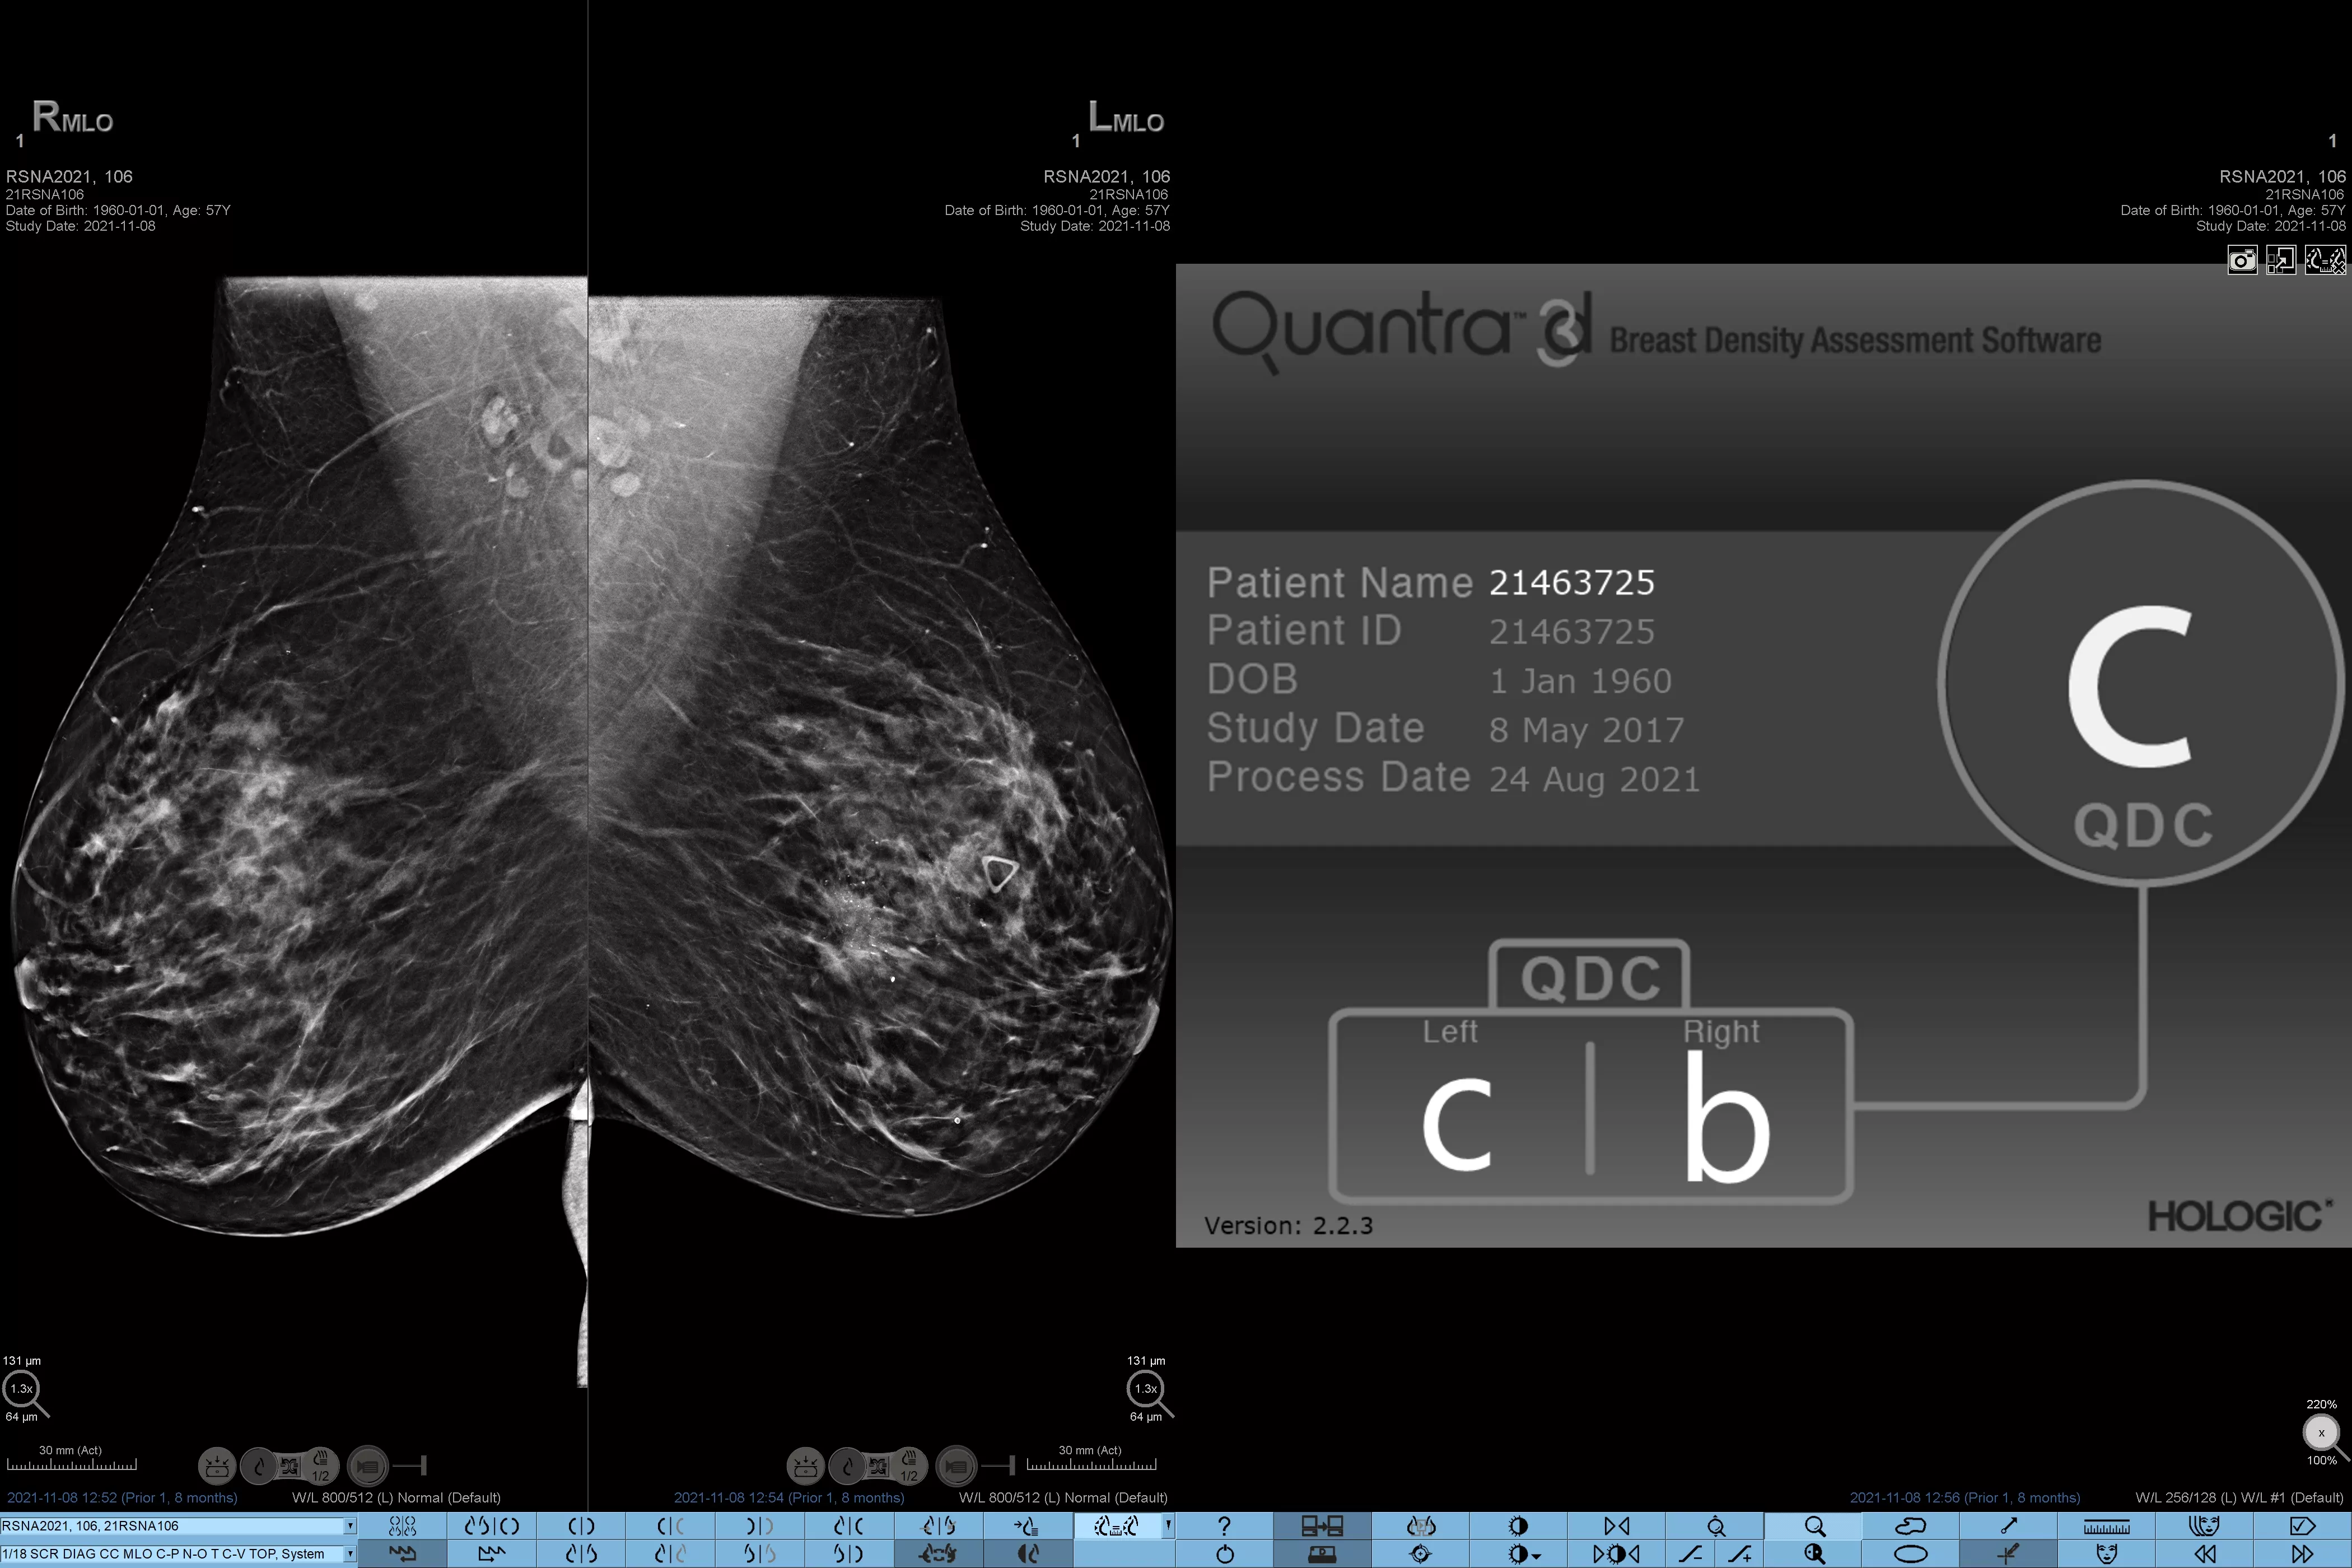

È noto che una maggiore densità del tessuto aumenta il rischio di tumore della mammella.1 È pertanto essenziale effettuare un'analisi accurata e obiettiva. Grazie alle funzionalità di machine learning, il software della tecnologia Quantra analizza le immagini 2D™ e di tomosintesi per evidenziare la distribuzione e l'aspetto del tessuto parenchimale. Classifica le mammelle in quattro categorie in base alla composizione, in linea con le indicazioni del BI-RADS Atlas dell'American College of Radiology (ACR), 5a edizione.2

Oltre al volume, la struttura e l'aspetto del tessuto fibroghiandolare possono svolgere un ruolo altrettanto importante nella previsione del rischio di cancro al seno.3-5 Analizzando e categorizzando la struttura e l'aspetto del tessuto mammario, la nostra tecnologia può fornire informazioni accurate che permettono di ottenere classificazioni coerenti e affidabili e di pianificare uno screening personalizzato.

*I punteggi si basano sulle categorie ACR BI-RADS, in conformità con le linee guida riviste del BI-RADS Atlas dell'American College of Radiation (ACR), 5a edizione. Per determinare la densità si tiene conto della struttura e dell'aspetto del tessuto rispetto al volume.

8. Categorie di densità del tessuto mammario descritte in ACR BI-RADS Atlas.